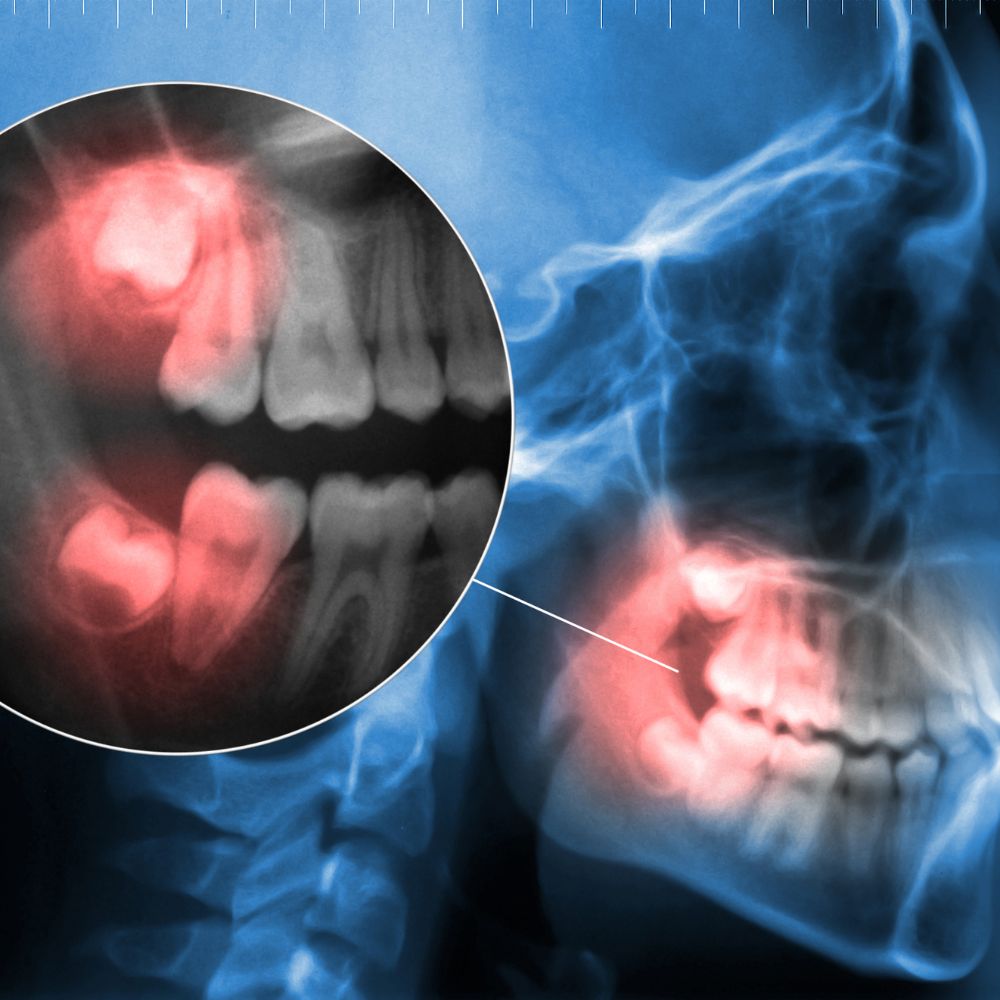

사랑니는 구강 내 맨 뒤쪽에 나오는 제3대구치로, 공간 부족, 비정상적 각도, 잇몸 염증, 인접치아 손상 등 다양한 문제를 유발할 수 있습니다.

특히 매복사랑니는 충치, 잇몸질환, 턱 통증, 얼굴 붓기 등 합병증 위험이 높아, 예방적 발치가 권장되는 경우가 많습니다.

- 전문의에게 시술받기, 사전 CT·파노라마 촬영